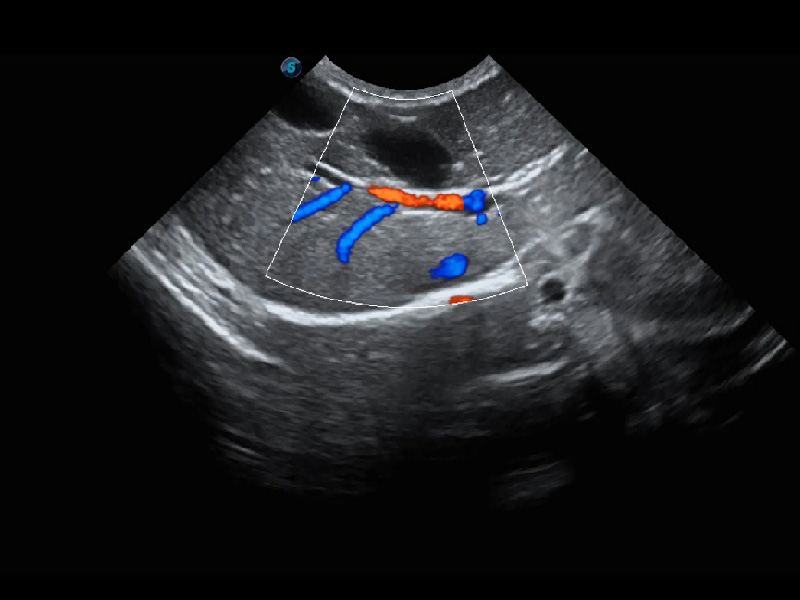

Micro F 显微血流成像

通过创新的Matrix E自适应滤波器和超长时间域算法,极大提升超低速微细血流的检出能力,同时更精准地滤除软组织和噪声信号,为兽用医生提供以往无法通过常规血流获得的疾病诊断信息。

(犬)肾脏血流